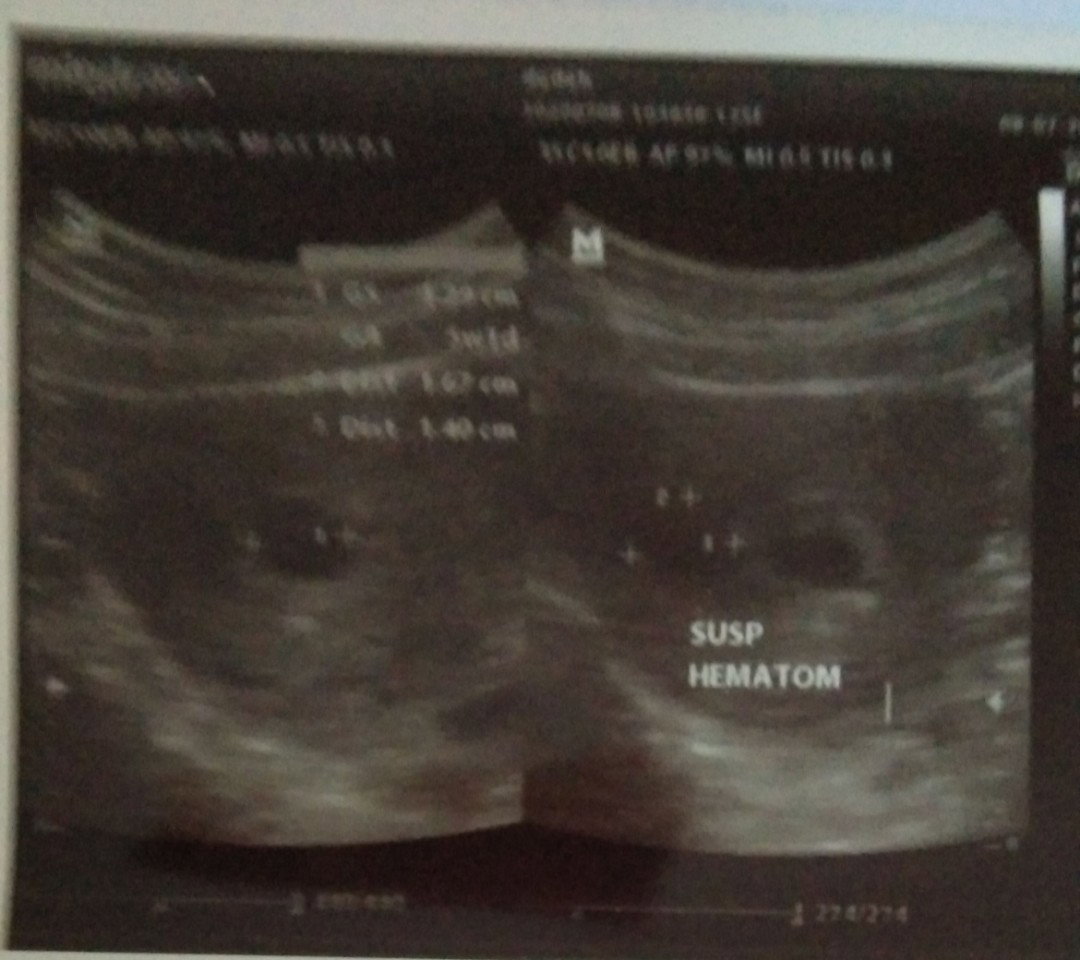

sush hematon

Bun, usia kandungan sya kta bidan 7 minggu, tpi pas usg 5 minggu, sedih pgi ini kluar darah, ntah ngflak...pas usg ada gumpalan darah dkt rahim,,hnya 50%kemungkinan jika kndungan kuat... bntu doanya smga kndunganku kuat sehat slalu